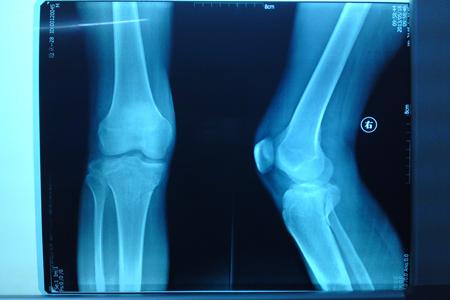

脛骨平臺(tái)骨折

脛骨上端與股骨下端形成膝關(guān)節(jié)。脛骨與股骨下端接觸的面為脛骨平臺(tái)。脛骨平臺(tái)是膝關(guān)節(jié)的重要負(fù)荷結(jié)構(gòu),一旦發(fā)生骨折,使內(nèi)、外平臺(tái)受力不均,將產(chǎn)生骨關(guān)節(jié)炎改變。由于脛骨平臺(tái)內(nèi)外側(cè)分別有內(nèi)、外側(cè)副韌帶,平臺(tái)中央有脛骨粗隆,其上有交叉韌帶附著,當(dāng)脛骨平臺(tái)骨折時(shí)常發(fā)生韌帶及半月板的損傷。